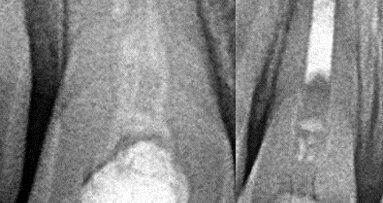

Dva dana ranije, u saobraćajnoj nezgodi, malu Marlenu udario je automobil. Na desnom gornjem centralnom sekutiću bila je prisutna fraktura gleđi i ...